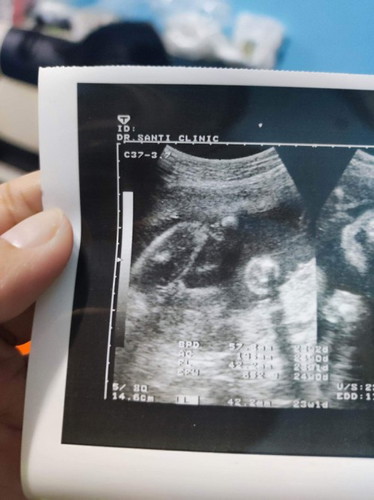

แม่ช่วยดูหน่อยจ้า

แบบนี้แม่ๆคิดว่าหญิงหรือชายค่ะ

น่าจะหญิงนะคะ